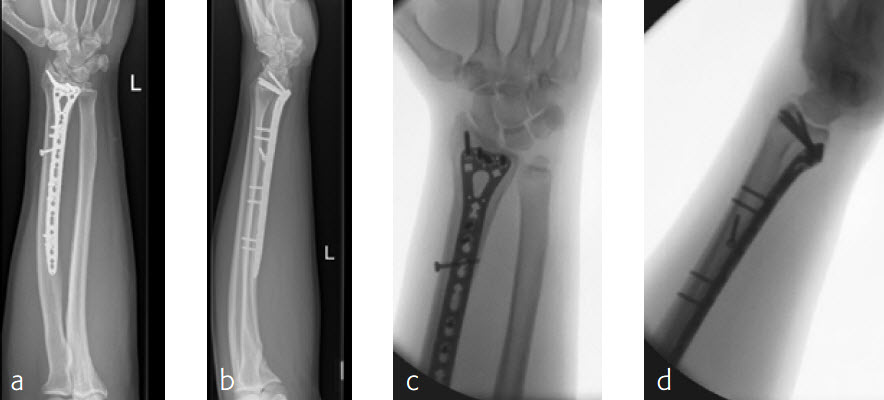

Case 3: Multifragmentary distal radius fracture with extension into the diaphysis

A 26-year-old man suffered a multifragmentary fracture of his left distal radius with extension into the diaphysis (AO23 C3.3) (Fig 1). The VA LCP Extra Long Two-Column plate was used for fixation (Fig 2). After initial immobilization, the plate provided a good postoperative fixation of the fracture.

The fracture showed primary bone healing without callus formation. At the 3-month follow-up, the patient was full weight bearing with excellent clinical function (Fig 3). The radiological follow-up can be technically challenging due to the correct focus of the central ray.